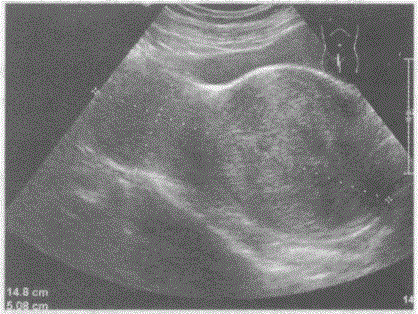

问题 临床资料:女,42岁,自述下腹坠胀,月经量增多3年余。 超声综合描述:子宫前位,宫颈部可见7.8cm×7.2cm低回声区,边界清晰,形态规则,内回声不均匀,呈漩涡状,向外突起,CDFI:周边可见少许血管绕行,呈动脉血流频谱。见下图及彩图105。 {图2} {图3} 超声提示:

选项 A.子宫颈妊娠 B.子宫颈肌瘤 C.子宫颈癌 D.阔韧带肌瘤

答案 B